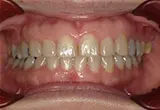

| 年齢/性別 | 50代女性 |

| 主訴 | 左下奥歯に痛みがある、全体的に治したい |

| 治療内容 | 全体的に歯周病やむし歯、根の治療を行い、仮歯を使用して咬合治療を実施。右下2本、左下1本の計3本を抜歯し、その後、右下に2本、左下に2本の計4本のインプラントを埋入しました。 |

| 治療期間 | 8か月 |

| 費用 | 2,106,500円税込 |

| リスク・副作用 | 炎症反応によって術後に腫れが生じることがあります。その程度は、手術の範囲や方法によって異なりますが、多くの場合、時間の経過とともに徐々に治まります。 ごく稀に、下顎奥歯の外科手術後に、唇や顎に痺れを感じることがあります。 |